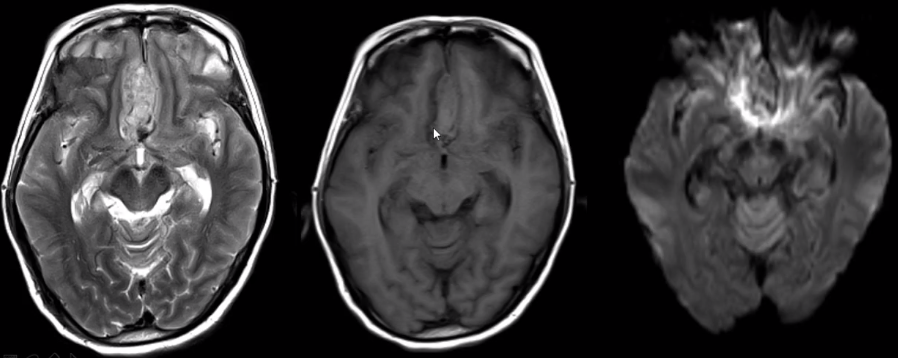

(3)静脉性脑梗死

MRI 表现与硬膜窦内血栓、静脉回流受阻造成的继发性脑实质改变有关:

脑实质改变包括水肿、出血灶。

脑白质(灰白质交界)出血。

DWI 表现不尽相同。

不同血管分布。

如下图可见案例:静脉性脑梗死与动脉性脑梗死对比

(上下滑动查看全部图片)